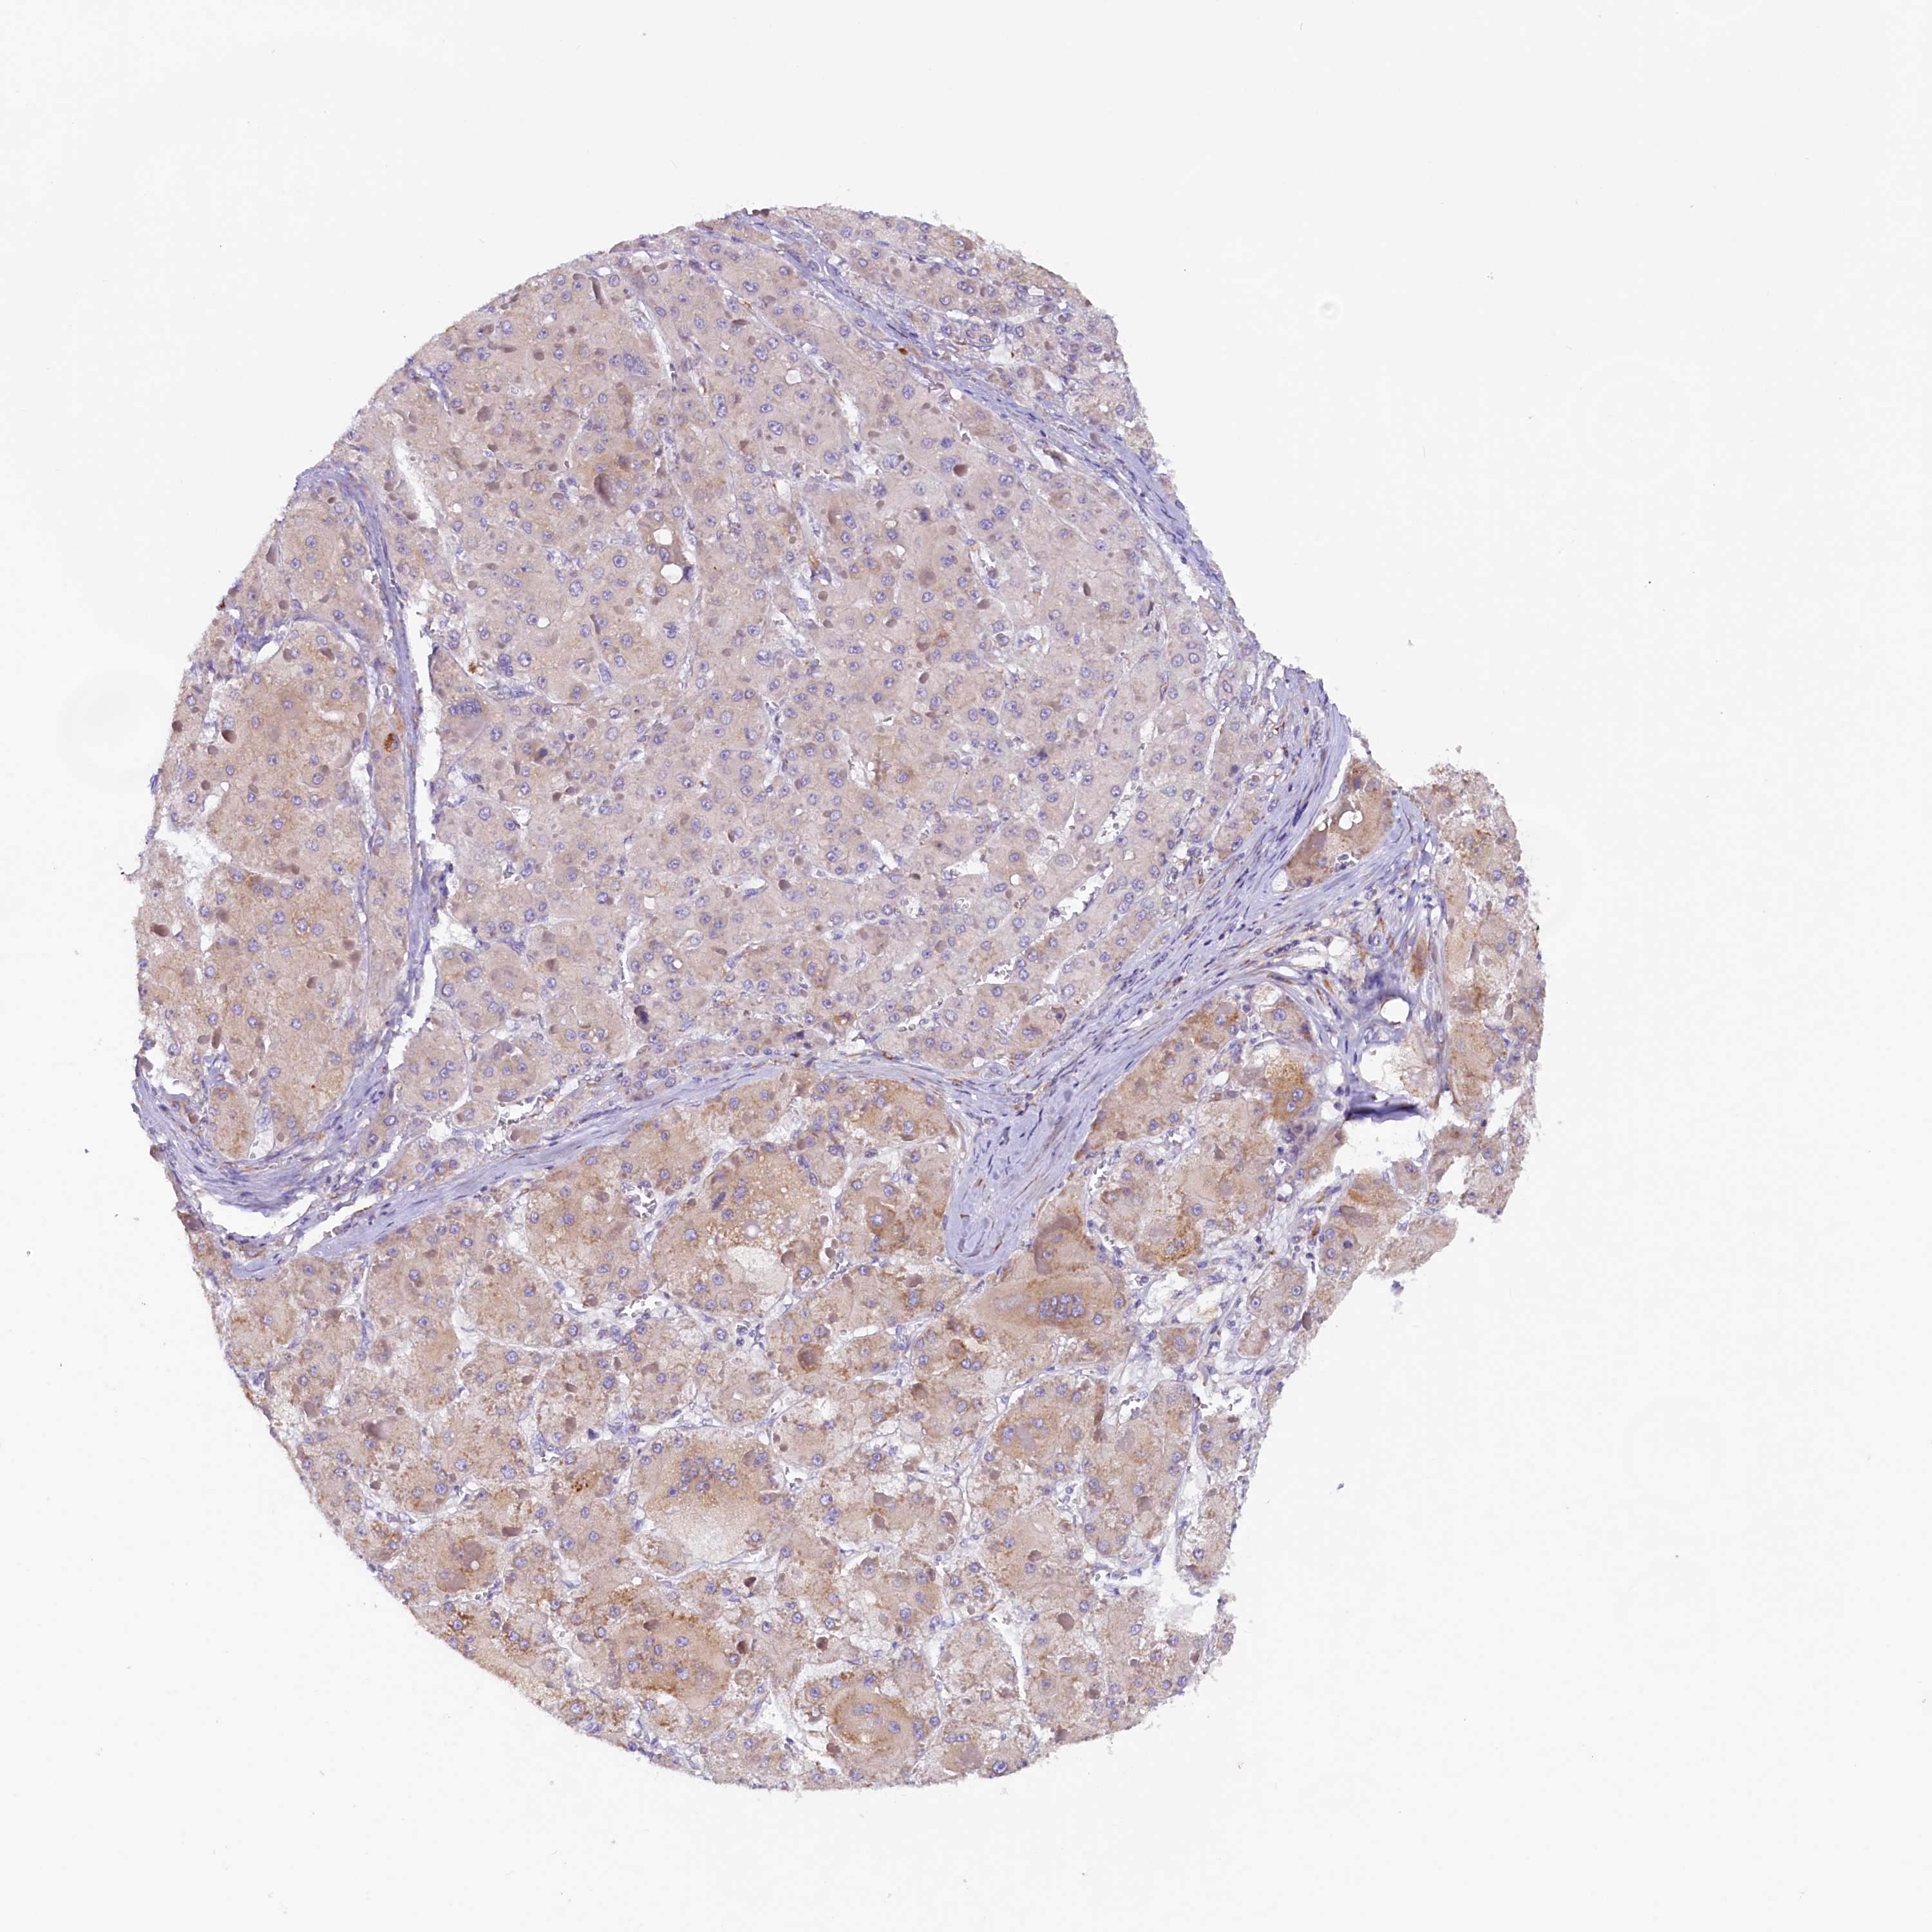

LIVER CANCER - Protein expressioni

A mouse-over function shows sample information and annotation data. Click on an image to view it in a full screen mode. Samples can be filtered based on level of antibody staining by selecting one or several of the following categories: high, medium, low and not detected. The assay and annotation is described here.

Note that samples used for immunohistochemistry by the Human Protein Atlas do not correspond to samples in the TCGA dataset.

Antibody stainingi

Antibody staining in the annotated cell types in the current human tissue is reported as not detected, low, medium, or high, based on conventional immunohistochemistry profiling in selected tissues. This score is based on the combination of the staining intensity and fraction of stained cells.

Each image is clickable and will lead to virtual microscopy that enables deeper exploration of all samples and also displays staining intensity scores, fraction scores and subcellular localization as well as patient and tissue information for each sample.

Antibody HPA042008

Staining

High

Medium

Low

Not detected

Intensity

Strong

Moderate

Weak

Negative

Quantity

>75%

75%-25%

<25%

None

Location

Nuclear

Cytoplasmic/membranous

Cytoplasmic/membranous,nuclear

Cholangiocarcinoma

Carcinoma, Hepatocellular, NOS